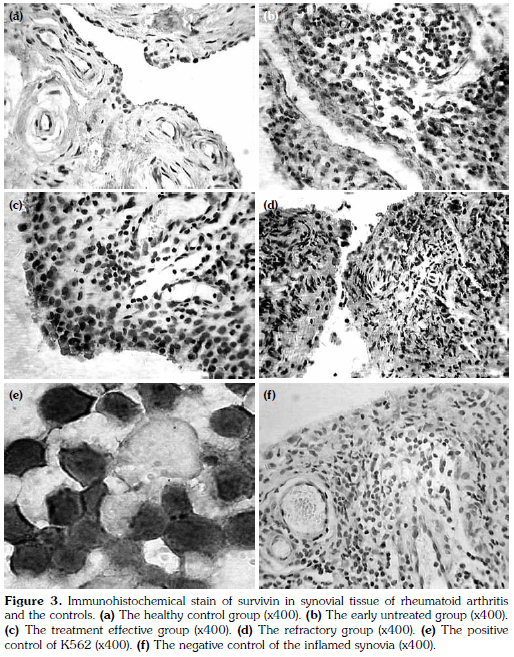

Fifty-one synovium samples were obtained from the 60 RA patients and the trauma joints of the 20 healthy control group, following joint replacement surgery or synovectomy. Specimens were fixed in 10% neutral-buffered formalin (pH 7.4) at 4 °C for 24 hours and embedded in paraffin. Four-micrometer thick tissue sections were used and dewaxed in xylene and rehydrated through decreasing concentrations of ethanol and water. Immunohistochemical staining for survivin expression was carried out using a standard immunoperoxidase technique (ABC-method). All slides were warmed up for 35 min to a temperature of 55 °C for dewaxing, boiled in 10 mM citrate buffer (pH 6.0) by microwave treatment (600 W) for 20 min for demasking the antigens. All stainings were performed in cover slides in combination with the prepared slides; K562 cells as positive control and one negative control were included. Once the slides with endogenous peroxidase was immersed in methanol with 0.03% hydrogen peroxide for 12 min, endogenous peroxidase activity was blocked. The primary antibody was incubated for 30 min at a temperature of 37 °C (dilution 1:200, GTX100052, USA). After washing with PBS-buffer, the secondary antibody was applied at room temperature for 12 min. The staining for survivin was visualized with the DAB kit (Beijing Zhong shan Golden Bridge Biotechnology Co., Ltd). The specimens were counterstained with hemalum. The stained specimens were viewed at an objective magnification of x200 and x400 by three investigators.

Cells stained brown were considered positive. With 50 cells per field, at least four fields were randomly observed under high magnification. The percentage of positive cells in total cells were calculated. Staining results were divided into: (i) negative (-), no significant difference between cell color and the background. (ii) Weakly positive (+), positive cells <10%. (iii) Positive (++), positive cells account for 10% ~50%. (iv) Strongly positive (+++), positive cells >50%.

Fifty-one synovial tissues were obtained from 60 patients with RA and 20 patients of the control group and were stained by immunohistochemical staining methods. The positive cases of expression of survivin in synovial tissue from the early untreated group was significantly higher than in the controls (Chi-square=11.18, p=0.00) and the effective group (Chi-square=6.75, p=0.04). The positive cases of expression of survivin of the refractory group was significantly higher than the treatmenteffective group (Chi-square=7.10, p=0.03) and the controls (Chi-square=13.93, p=0.00). There was no significant difference between the refractory group and the early untreated group (Chi-square=0.31, p=0.86). Expression of survivin in synovial tissues from the four groups are shown in Figure 3a-d. The positive and negative controls are shown in Figure 3e, f. The positive cases of each group are shown in Table 4, 5.